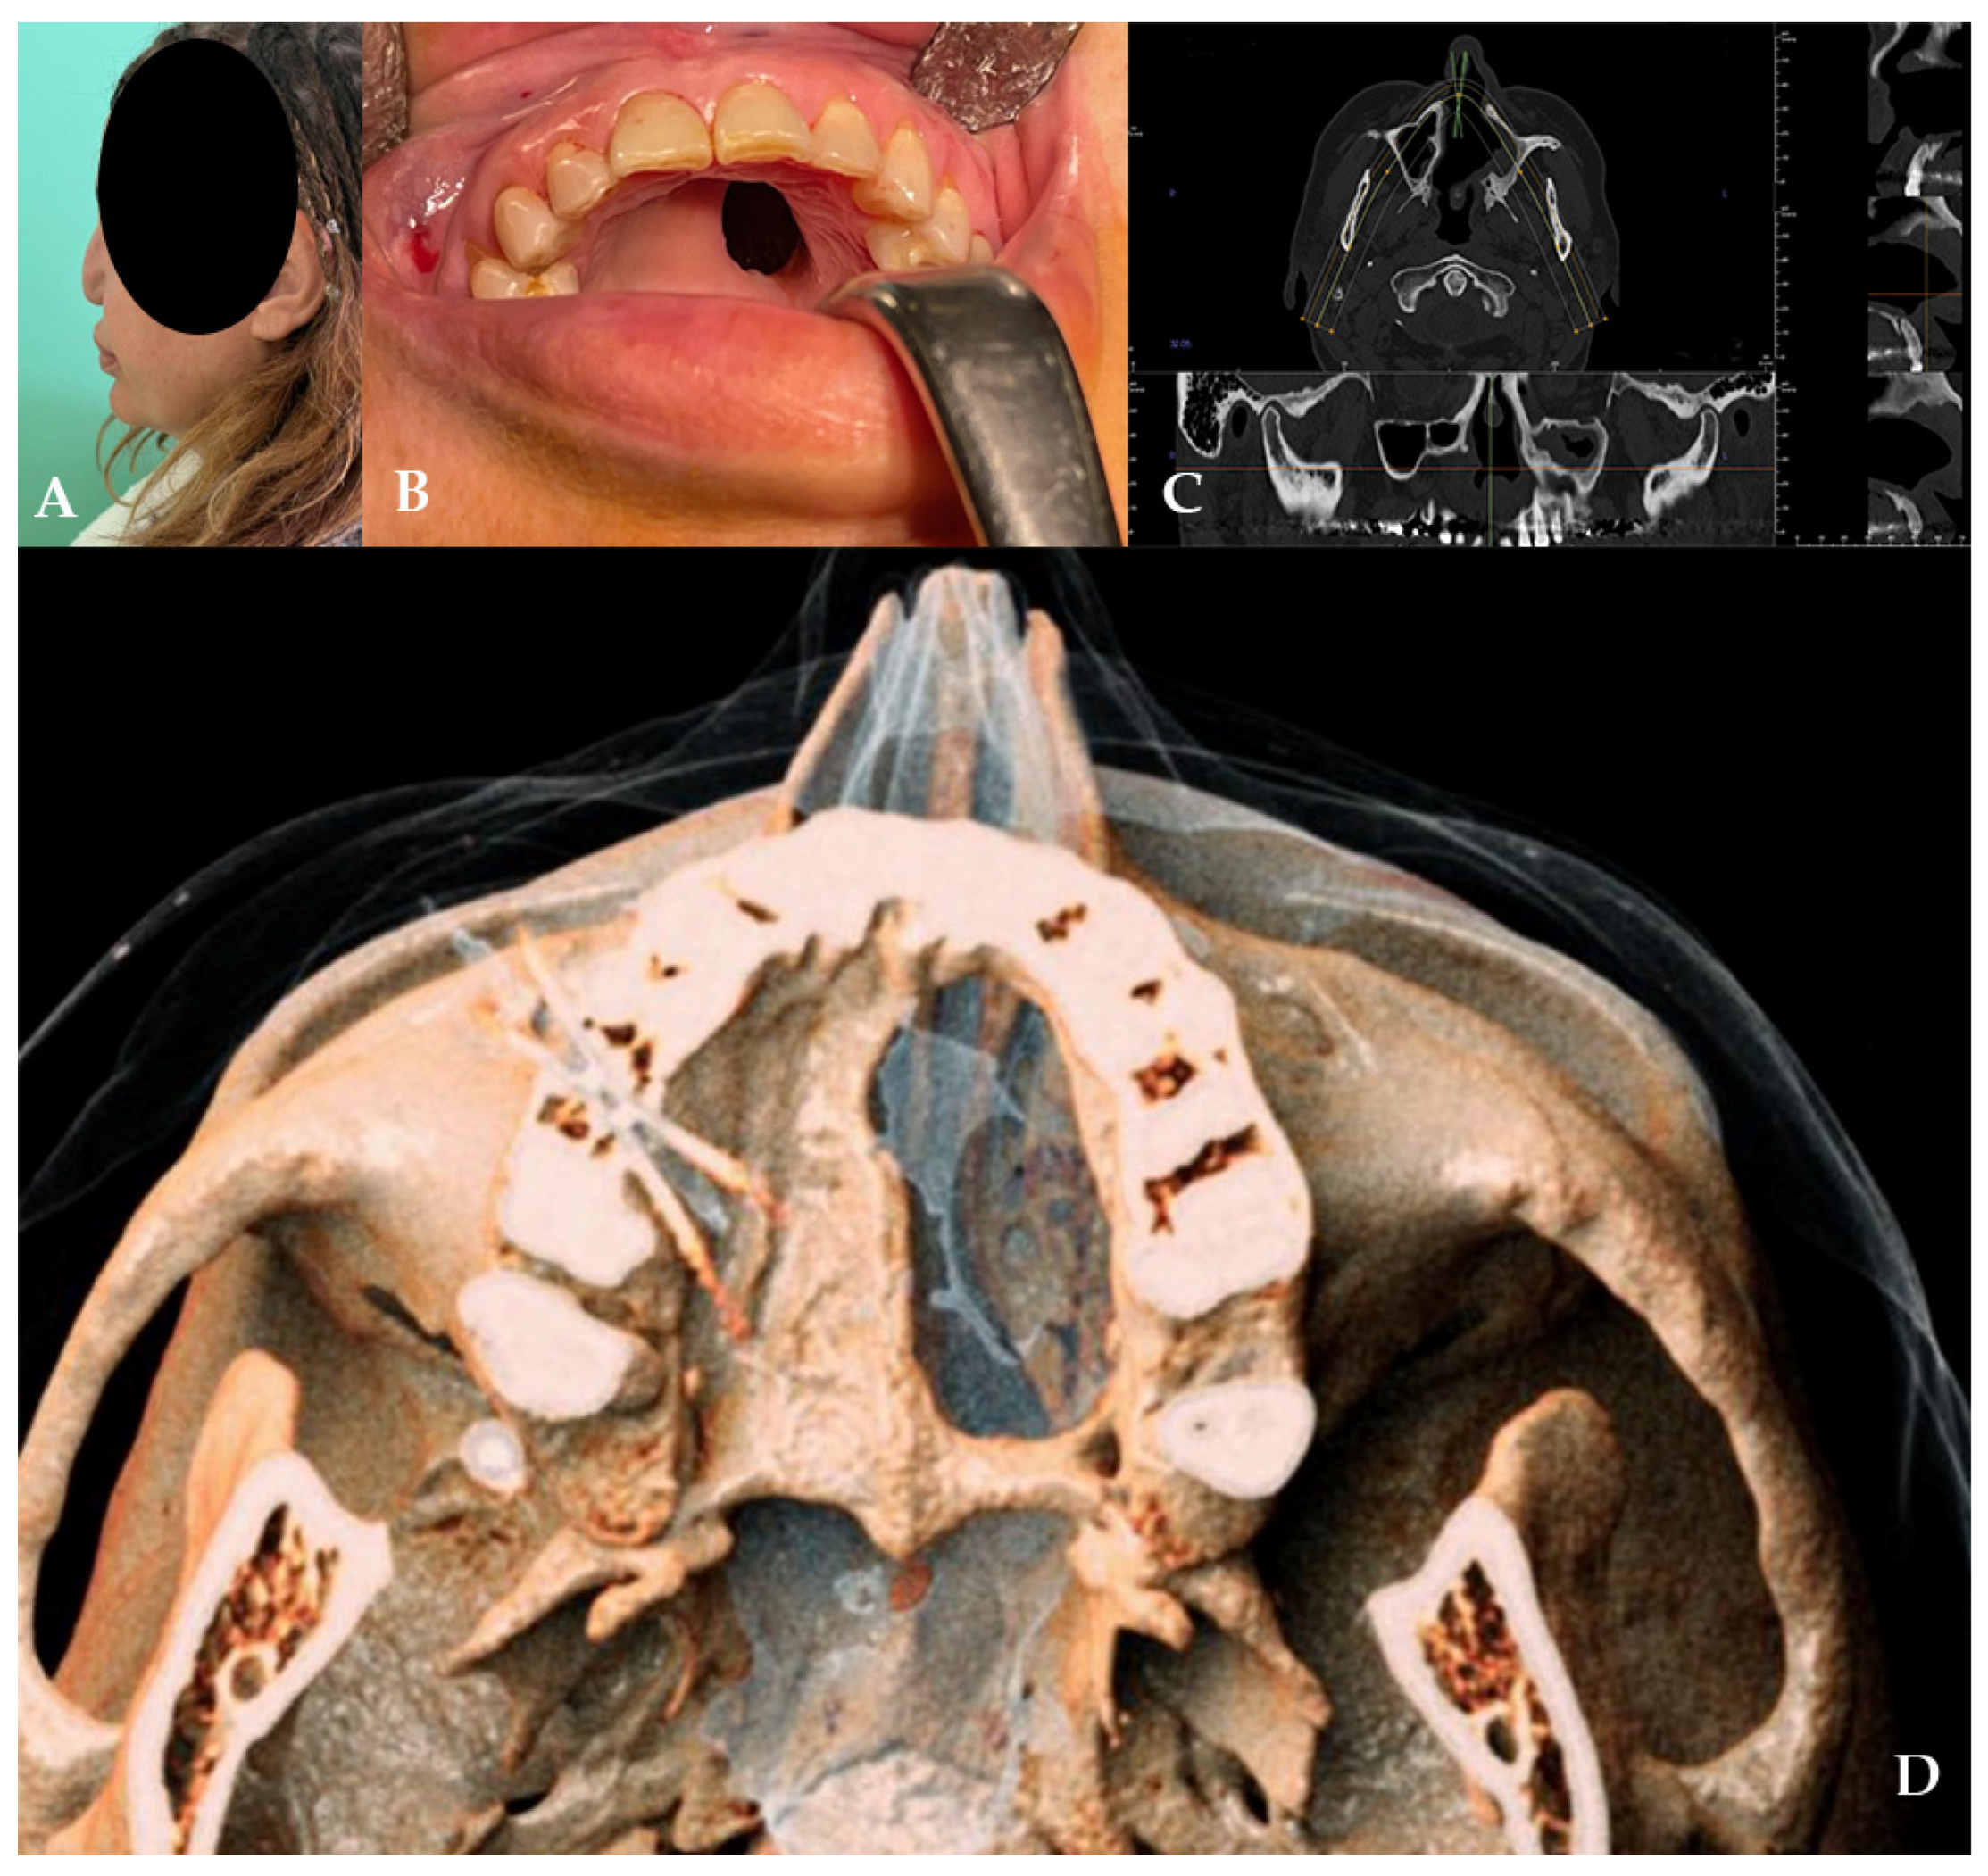

2.3. Case 3

A 40-year-old female patient came to our attention in 2022, presenting a palatal/oro-nasal fistula measuring 2 cm in diameter along the major axis, with atrophic and burned soft tissues surrounding the lesion (Ia according to the Okay et al. classification [14]), as well as the loss of the right orbital floor and the eye. The patient was surgically treated to remove the inflamed and necrotic bone in another center, with the reconstruction of the orbital floor using a mesh. A wide bony and cartilaginous septal destruction with communication of the nasal cavity and collapse of the nasal pyramid was also shown at the clinical examination. Speech disturbances, rhinolalia, and eating difficulties were shown. In 2023, the patient underwent surgical intervention to reconstruct the palate. Under general anesthesia, the surgery was performed, starting with a Le Fort I osteotomy preceded by preplating to achieve the correct repositioning of the fragment. A careful dissection of the nasal and palatal mucosa was performed after the down fracture. A temporalis muscle rotation flap was harvested on the right side. The operation lasted three hours in the oro-tracheal tube. A nasogastric tube was placed and kept in place for seven days with standard antibiotic and anti-inflammatory therapy. The patient was discharged after four days.

The patient attended follow-up appointments at 1 week, 1 month, 6 months, and 1 year, with complete resolution of the fistula, improved speech capacity, and no difficulties with eating (Figure 7).

Figure 7. (AE) Radiographic and 3D reconstruction using InVivo6® and Anatomage Table EDU vers.8® (Santa Clara, CA, USA) software. DICOM files were imported in InVivo® (California, USA) software to obtain the axial, cross, and panorex sections. Afterwards, the DICOM files were imported into Anatomage Table® (Santa Clara, CA, USA) to obtain the 3D rendering. (F) Clinical presentation of the oro-nasal communication. (GJ) Radiographic and 3D reconstructions using InVivo6® and Anatomage Table EDU vers.8® (Santa Clara, CA, USA) software at the one-year follow-up. (K) One-year clinical follow-up.